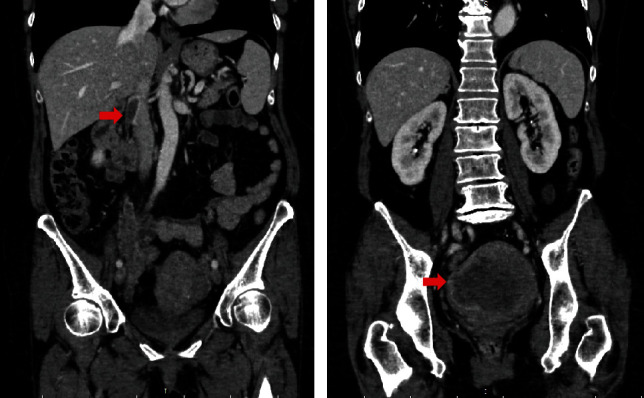

未分化子宫肉瘤(undifferentiated子宫sarcoma, UUS)是一种罕见且具侵袭性的子宫肿瘤。因此,我们对UUS作为心脏转移的主要部位知之甚少。我们报告一例66岁女性,子宫肌瘤病史30年,因子宫大肿瘤及心脏肿块住院治疗。尽管我们使用超声、心脏计算机断层扫描和磁共振成像等成像方式研究了心脏肿块,但很难确定肿块是转移灶还是血栓。心脏肿块通过手术切除以评估组织特征,后来因其外观被确定为肿瘤。病理结果显示UUS向右心室扩散。我们在手术后尝试化疗;然而,病情进展很快,患者于入院第49天死亡。在这篇报告中,我们描述了一个诊断困难且疾病进展迅速的UUS心脏转移的病例。

Although cardiac metastasis of malignant tumors has often been reported, undifferentiated uterine sarcoma (UUS) is a rare and aggressive uterine tumor. Thus, little is known of the UUS as a primary site of cardiac metastasis. We report a case of a 66-year-old woman, with a history of uterine myoma for 30 years, who was hospitalized with a large uterine tumor and cardiac masses. Although we investigated cardiac masses using imaging modalities, such as ultrasound, cardiac computer tomography, and magnetic resonance imaging, it was challenging to determine the masses as metastasis or thrombi. Cardiac masses were removed by surgery to assess the tissue characteristics and were later identified as tumors due to their appearance. Then, pathological findings revealed that UUS spreads to the right ventricle. We attempted chemotherapy after surgery; however, the disease progressed very quickly and the patient died on the 49th day of admission. In this report, we described the case of a patient with a difficult diagnosis and rapid disease progression of cardiac metastasis from UUS.